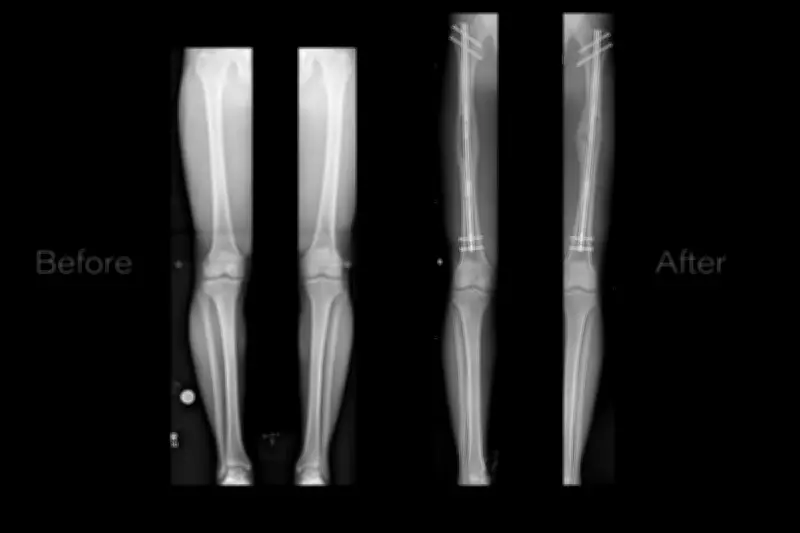

In 2020, Brada produced a BBC documentary exploring the struggles of individuals so distressed by their height that they considered extreme measures. The procedure involves breaking leg bones, gradually separating them, and allowing healing to achieve added inches. While sophisticated and beneficial for those with limb discrepancies, it is an arduous process testing physical, mental, and financial limits. Recently, The Times highlighted a pioneering case: Alfie Phillips, a nine-year-old with a shorter right leg, underwent magnetic lengthening by British scientists. Brada acknowledges people's right to address their issues as they see fit but questions what it reveals about societal pressures that drive such drastic actions.